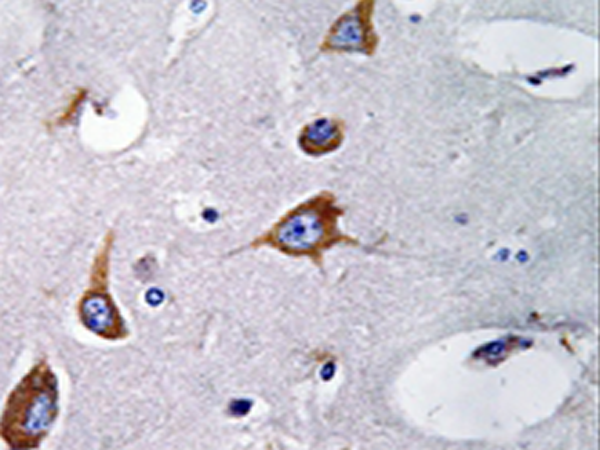

IHC positive control: |

Human brain tissue |

IHC Recommend dilution: |

50-100 |